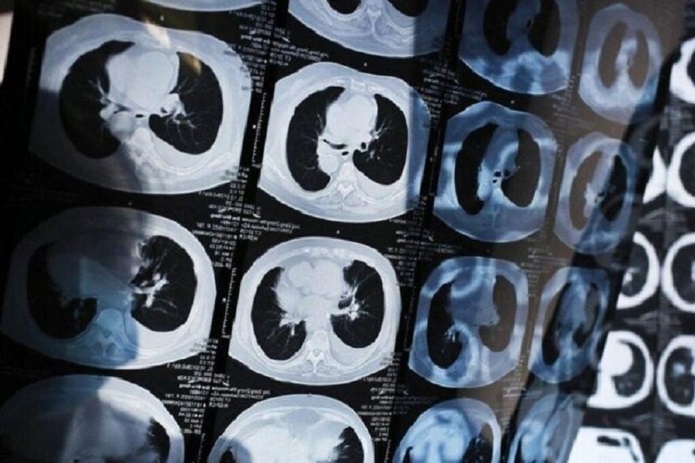

تشخیص سرطان ریه در مراحل اولیه

دانشمندان دانشگاه پکن ابزاری مبتنی بر هوش مصنوعی برای تشخیص سرطان ریه در مراحل اولیه توسعه دادند.

جامعه ۲۴- دانشمندان چینی از توسعه ابزار آزمایشی مبتنی بر هوش مصنوعی برای تشخیص سرطان ریه خبر دادهاند. محققان اظهار کردهاند این سیستم هوش مصنوعی ممکن است در تشخیص زودهنگام سرطان ریه در مراحل اولیه یا غربالگری در مقیاس بزرگ نقش مهمی داشته باشد.